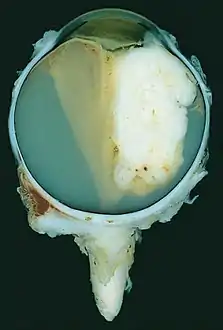

| A pathology specimen of a retinoblastoma tumor from an enucleated eye of a 3-year-old female | |

Large exophytic white tumor with foci of calcification producing total exudative retinal detachment

Morphology

Gross and microscopic appearances of retinoblastoma are identical in both hereditary and sporadic types. Macroscopically, viable tumor cells are found near blood vessels, while zones of necrosis are found in relatively avascular areas. Microscopically, both undifferentiated and differentiated elements may be present. Undifferentiated elements appear as collections of small, round cells with hyperchromatic nuclei; differentiated elements include Flexner-Wintersteiner rosettes, Homer Wright rosettes,[29] and fleurettes from photoreceptor differentiation.[30]